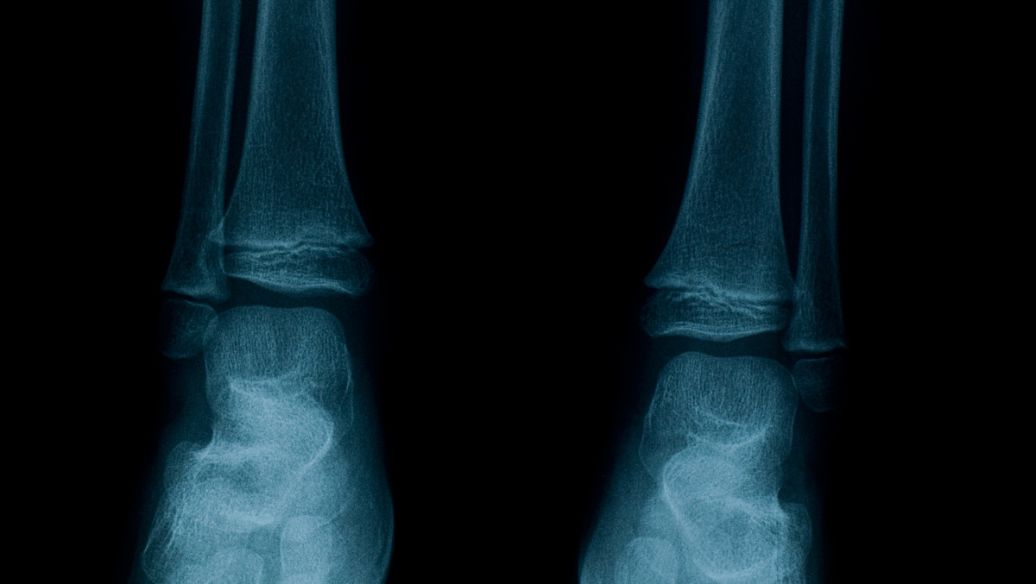

?腫瘤所致骨軟化癥(OOM)初起時癥狀無特異性,出現(xiàn)骨與肌肉疼痛、疲倦乏力,繼而發(fā)生骨折。兒童少年常有步態(tài)異常、下胺彎形。低腎小管最大磷酸鹽重吸收力/生長激素釋放激素(TmP/GRH),低磷血癥。腸對磷吸收欠佳。血清1,25一(OH)2一D3較低。影像學(xué)見骨軟化癥。引起疾病的腫瘤多較小,生長緩慢,多數(shù)屬源于中胚層的腫瘤,但亦見于癌癥。腫瘤切除后疾病好轉(zhuǎn)。

初起時癥狀無特異性,出現(xiàn)骨與肌肉疼痛、疲倦乏力,繼而發(fā)生骨折。兒童少年常有步態(tài)異常、下胺彎形。低腎小管最大磷酸鹽重吸收力/生長激素釋放激素(TmP/GRH),低磷血癥。腸對磷吸收欠佳。血清1,25-(OH)2-D3較低。

證實診斷的依據(jù)是檢出并定位基礎(chǔ)腫瘤。必須考慮到其他腎臟磷酸鹽流失病?;颊?尤其是成人)既往血清磷酸鹽水平正常一般支持診斷為TIO。由于腫瘤體積較小且位于隱蔽部位,常規(guī)成像技術(shù)很難對其定位。間葉腫瘤通常表達生長抑素受體,因此通過111銦噴曲肽閃爍成像(放射性標(biāo)記的生長抑素類似物奧曲肽的掃描技術(shù))可以定位部分患者的腫瘤。全身MRI、(18F)FDG-PET/CT等其他影像學(xué)檢查也可用于定位腫瘤。體靜脈采樣檢測FGF23也已用于定位致病腫瘤,但該技術(shù)更適合確定所識別的腫塊是否產(chǎn)生FGF23。腫瘤體積較小且位于骨骼這些特點限制了識別和定位腫瘤的能力,推定診斷為TIO患者的腫瘤檢出率為65%-80%。